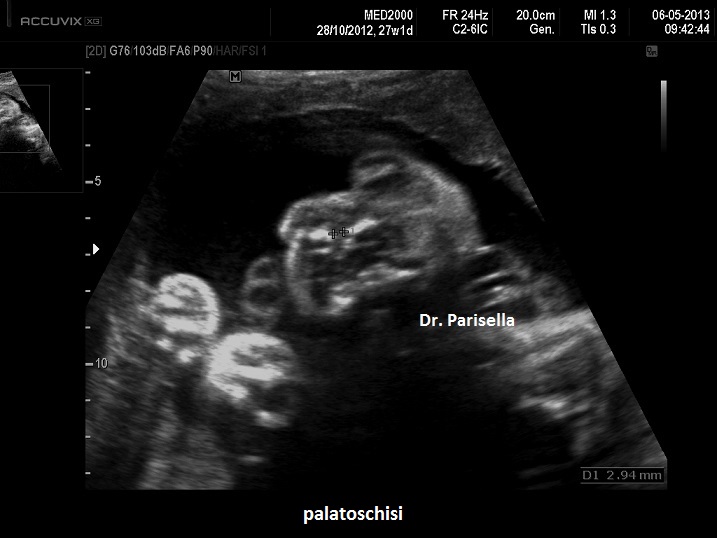

Le anomalie cranio-facciali comprendono aglossia (assenza della lingua), microstomia, micrognatia, palatoschisi.